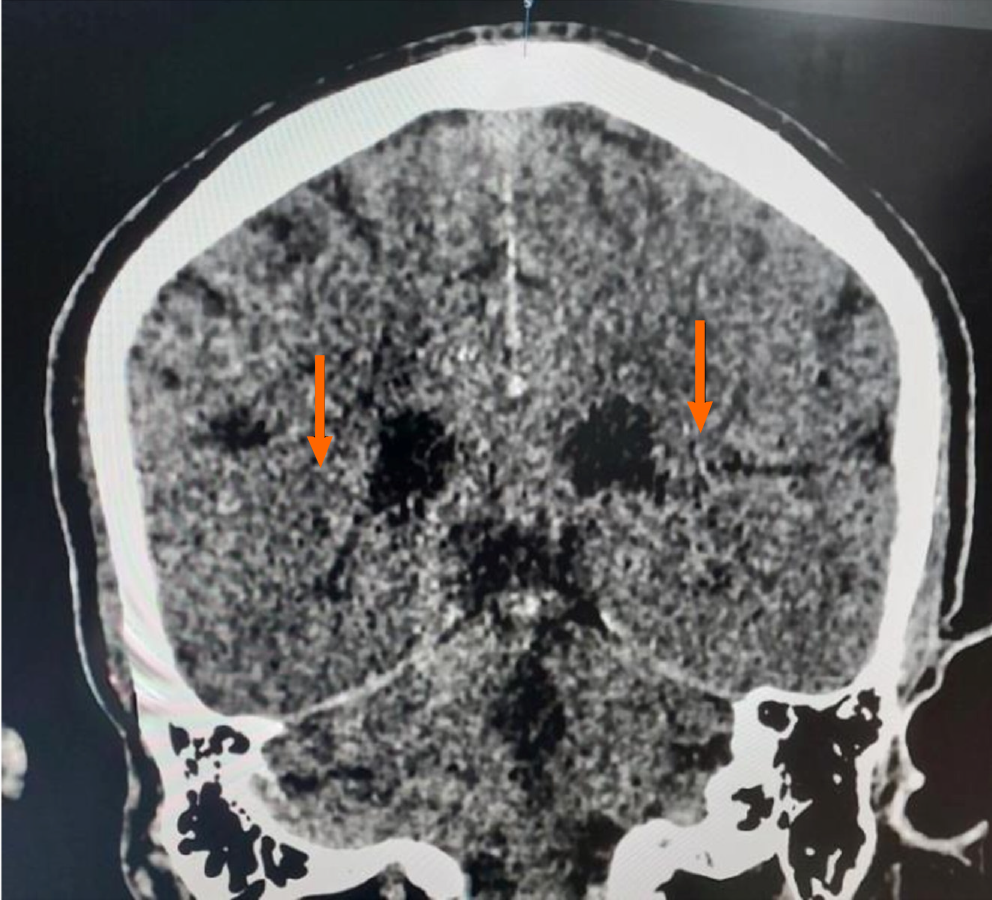

The imaging features of HIBI are often overlooked. The features of HIBI in computed tomography (CT) range from subtle loss of grey-white differentiation to low density generalized edema[22] (Figure 2). The density usually drops to 22–24 Hounsfield units (HU). The deep grey matter (i.e. basal ganglia, thalamus), hippocampi, cerebellum and perirolandic and occipital cortical grey matter appear hypodense on CT[7,22]. These structures are more susceptible because they are more metabolically active[2]. The reversal sign is due to the reversal of normal relative CT attenuation of grey and white matter[21]. The grey matter density decreases to 24 HU (normal: 37-45 HU) while that of white matter is more than 24 HU (normal: 20-30 HU). The pseudo-subarachnoid hemorrhage sign is higher attenuation in the basal cisterns and cortical sulci on a background of diffuse, hypoattenuating brain parenchyma. The white cerebellum signal is due to the cerebral edema contrasting with the hyperdense normal cerebellum.

Figure 2

Figure 2 Computed tomography image of brain showing subtle loss of grey-white differentiation and effacement of basal ganglia (orange arrows) in a patient post-cardiac arrest.